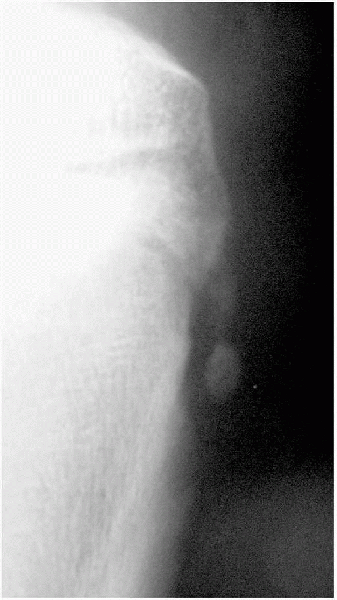

Radiographs must include a tunnel or notch view to avoid missing the typically posterior lesion (Fig. 5-17).

Plain radiographs, bone scans, or MRIs can reveal lesion staging (Fig. 5-18).